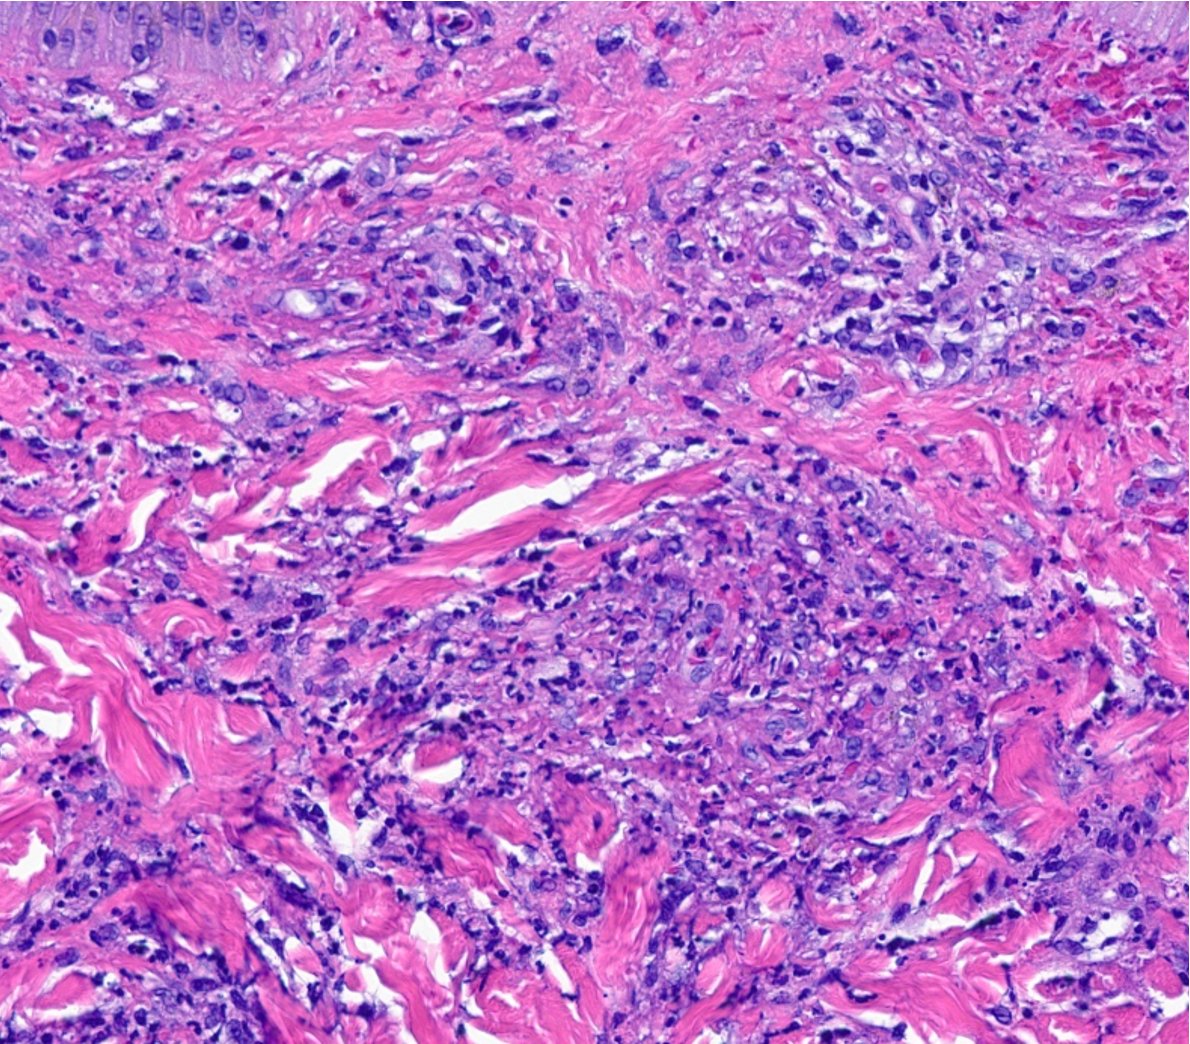

LANGERHANS CELL SARCOMA: Rare tumor of dendritic family often in dermis/subcutis. Sheets of bizarre pleomorphic/epithelioid cells. Rare dx not to forget about! (+) Langerin, S100, CD1a. #bstpath Jerad Gardner, MD @histiocytosisX Steven Billings, MD Scott Lauer, MD Rajiv M. Patel, M.D.